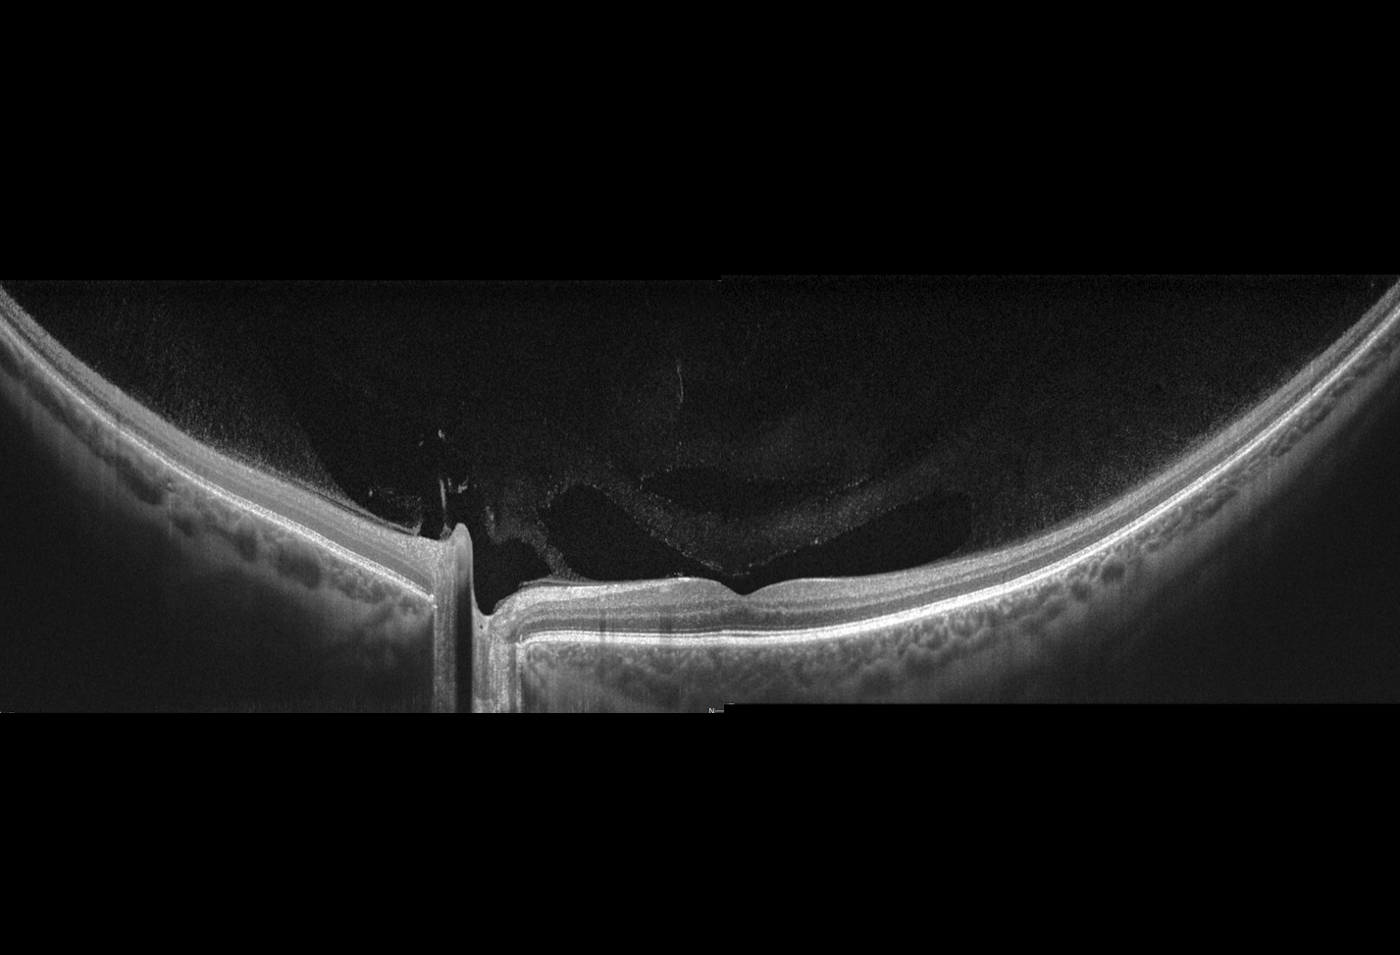

Netzhaut:

- Bis zu 12 X 12 mm Scanbereich

Vorderabschnitt:

- Integriertes Vorderabschnittsmodul (5 X 5mm)

- Autom. Pachymetrie

- Analyse des Kammerwinkels